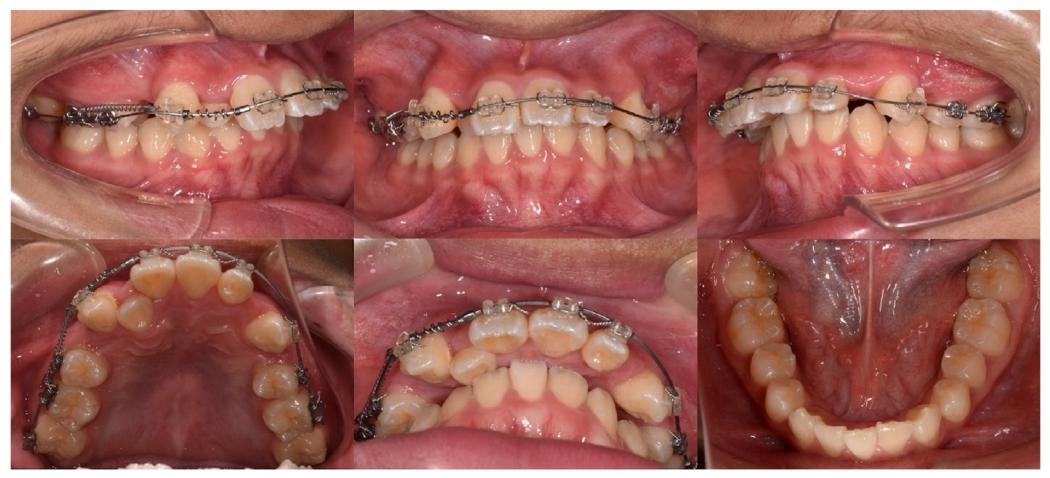

3. 阻生牙牵引与间隙利用(4-14个月)

✅ 开圈弹簧拉开#11与#13间隙,为#12“腾出位置”

✅ 轻力牵引+ISW弹性引导,逐步将阻生的#12纳入牙弓

第三月可见开圈弹簧为阻生牙创造间隙

4. 反锁合攻坚(14个月时)

✅ #17托槽施加垂直偏移,压低3mm解除与#47的咬合干扰

✅ 配合颌间弹性牵引,纠正颊舌向错位

第14月垂直偏移装置特写